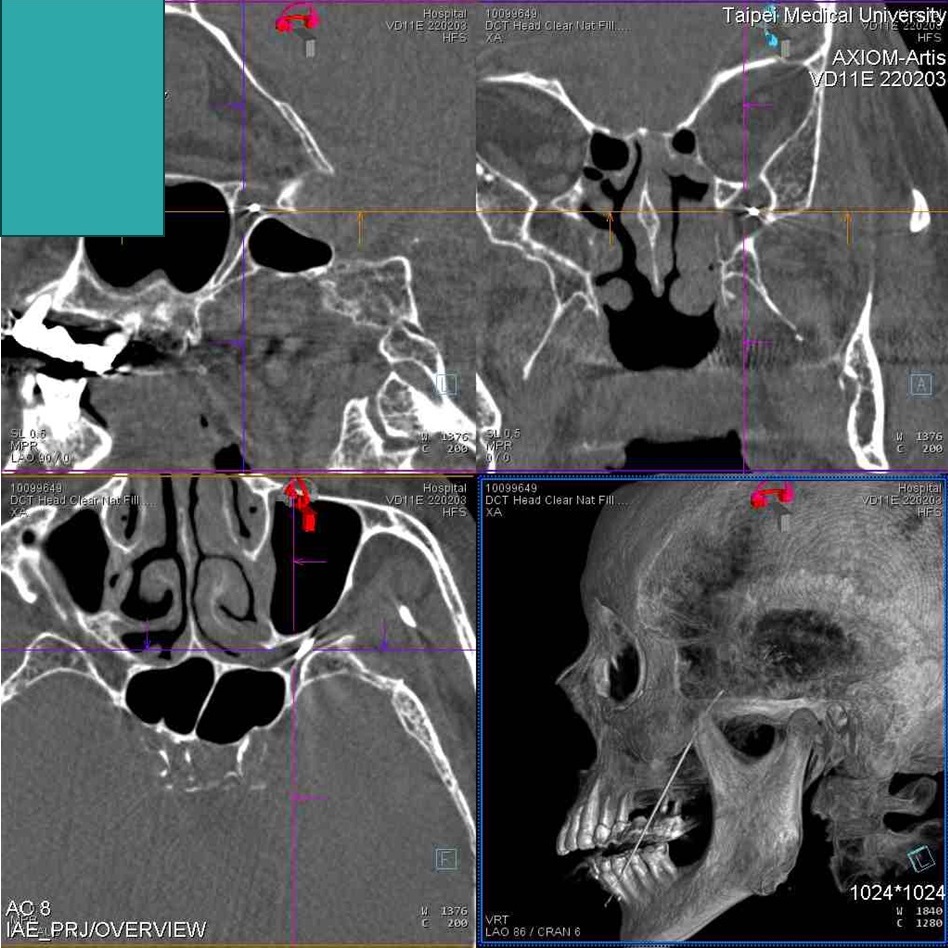

其中,高頻熱凝神經阻斷手術是使用影像導引穿刺,只有類似抽血的針孔,沒有切割傷口,相較於傳統的經顱減壓手術風險較低,是三叉神經痛患者的最佳選擇之一。而雙和醫院目前採用新型的顱底外神經孔分支獨立觸及手術技術,成效與傳統經卵圓孔穿刺入顱內的方式相當,大幅降低顱內出血與併發感染等風險。

▲透過手術抑制腦部髓鞘跳躍式傳導的不正常放電,藉此達到阻斷疼痛之效果。(圖/雙和醫院提供)

林嘉祥醫師解釋,高頻熱凝的治療技術又可分成兩項,其中低溫脈衝的神經調控治療,溫度控制小於攝氏42度,乃透過高能量的磁場效應去調控神經,進而穩定神經,達到止痛效果;然而,低溫脈衝相較高溫熱凝的手段通常成效稍低,且復發率稍高,但好處是不會損傷神經;另一種則是高頻熱凝神經阻斷手術,治療溫度約在攝氏60度到65度之間,有時甚至提高到攝氏80度到90度,利用高溫把三叉神經的髓鞘部分燒灼掉,抑制透過髓鞘跳躍式傳導的不正常放電以達到阻斷疼痛之效果。